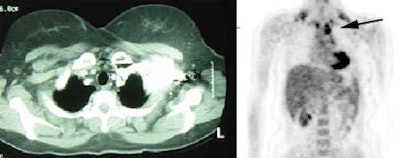

Metastatic melanoma: The patient shown below had a history of a lower extremity melanoma. CT imaging performed as part of the patient's evaluation revealed no evidence of metastatic disease. A FDG PET study demonstrated the presence of multiple lymph node metastases involving the supraclavicular and mediastinal nodes (black arrow). Beam hardening artifact from the I.V. contrast bolus obscured adequate evaluation of these regions on CT. PET imaging provides an excellent whole body survey and is a very sensitive exam for detecting melanoma metastases. Case courtesy of CTI PET Systems, Inc. |